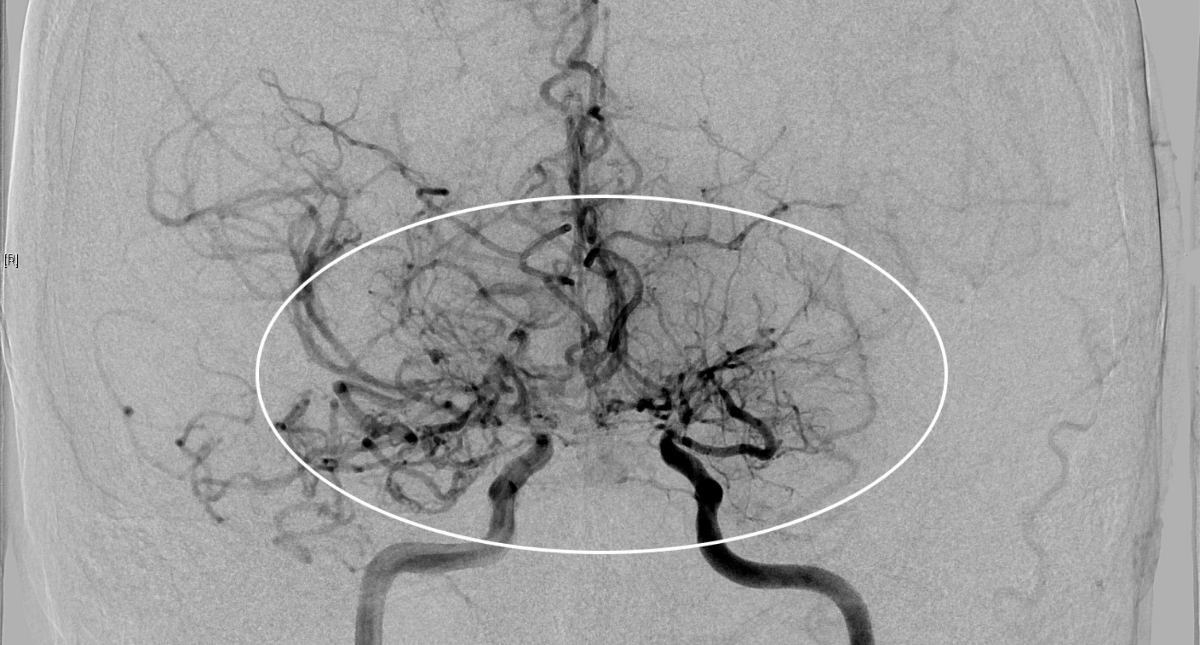

Khi nhập viện tại khoa Ngoại thần kinh, các xét nghiệm chuyên sâu gồm MRI tưới máu não và chụp mạch số hóa xóa nền (DSA), xác định bệnh nhân mắc Moyamoya – một bệnh lý mạch máu não hiếm gặp có tính chất tiến triển.

Các mạch máu não của bệnh nhân nhìn như “làn khói thuốc lá” trên phim chụp MRI.

Tại Bệnh viện đa khoa Medlatec, qua thăm khám lâm sàng, bệnh nhân không có dấu hiệu thần kinh khu trú hay tăng áp lực nội sọ. Để làm rõ nguyên nhân, bác sĩ chỉ định chụp cộng hưởng từ (MRI) sọ não. Kết quả MRI cho thấy, hình ảnh tổn thương hẹp tắc động mạch cảnh trong hai bên và các nhánh của đa giác Willis, xung quanh hình thành tuần hoàn bàng hệ với nhiều mạch máu nhỏ bất thường.

Đồng thời, trên chuỗi xung FLAIR, xuất hiện những dải tín hiệu sáng chạy dọc theo rãnh cuộn não, gợi hình ảnh “dây thường xuân” len lỏi trên bề mặt, phản ánh sự gia tăng tuần hoàn bàng hệ màng mềm để bù đắp cho tình trạng thiếu máu não do tắc nhánh mạch não. Bên cạnh đó, bác sĩ cũng phát hiện một hình ảnh tổn thương cũ ở vùng trán trái, là biến chứng của bệnh lý Moyamoya.

Theo BSCKI.BSNT Phạm Thị Yến, Chuyên khoa Chẩn đoán hình ảnh, Hệ thống Y tế Medlatec, trong chẩn đoán bệnh lý Moyamoya, chẩn đoán hình ảnh có vai trò rất quan trọng, giúp bác sĩ phân biệt với các bệnh lý gần tương tự như: xơ vữa động mạch, viêm màng não, chấn thương đầu…

Chẩn đoán hình ảnh phát hiện tình trạng hẹp hoặc tắc nghẽn phần cuối của động mạch cảnh trong sọ, rồi lan rộng ra các động mạch não trước, não giữa, não sau; phát hiện mạng lưới mạch máu bất thường ở vùng lân cận của các tổn thương dạng “làn khói thuốc”. Bệnh Moyamoya nếu không được phát hiện và điều trị kịp thời có thể dẫn đến đột quỵ, tàn phế hoặc tử vong.